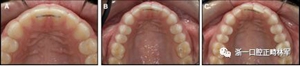

圖5.尖牙到尖牙的弓絲仍然固定在兩端,拱形偏斜和尖牙相反方向的扭矩:A,正面視圖; B,咬合面視圖(Rick Booth博士提供)。

圖6.尖牙到尖牙弓絲在切牙處向下偏斜(可能來自咬合力),導致通過尖牙的擴張:A,正面視圖; B,咬合面視圖。